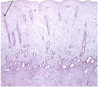

vagina